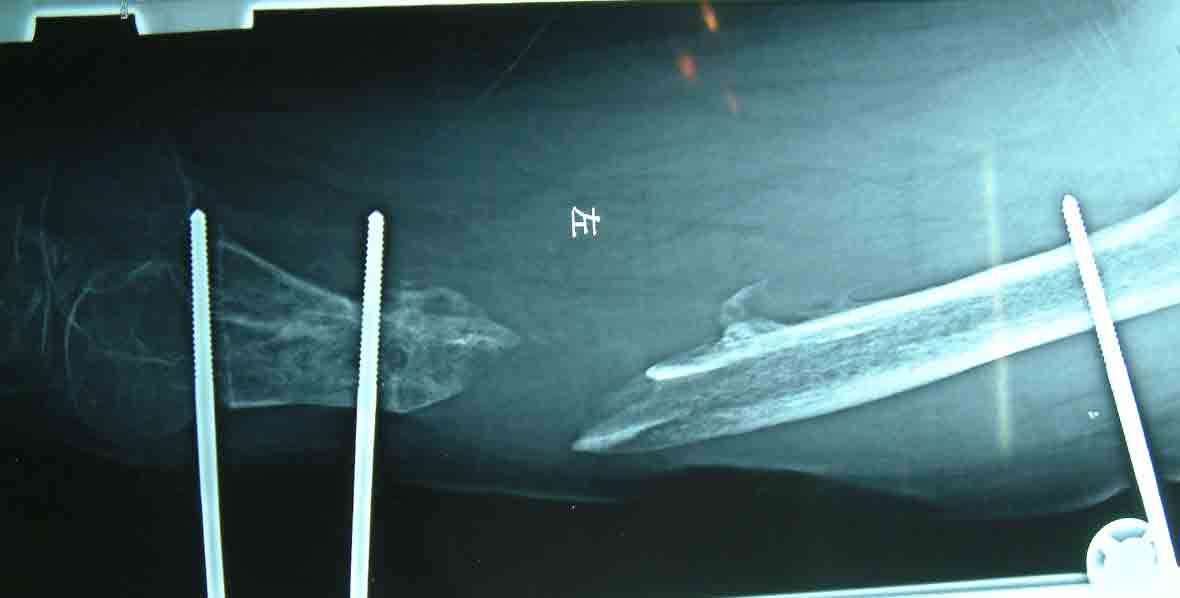

采用短缩的方法,将断端互相接触,植自体骨,

术后X

术后注射红骨髓和BMP